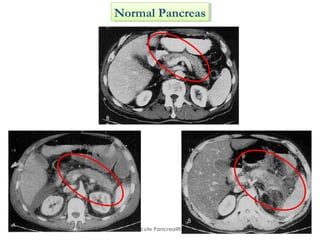

Normal PancreasNormal Pancreas

CT FindingsCT Findings

• Pancreas

– Pancreatic enlargement

– Decreased density due to edema

– Intrapancreatic fluid collections

– Blurring of gland margins due to inflammation

• Peripancreatic

– Fluid collections and stranding densities

– Thickening of retroperitoneal fat